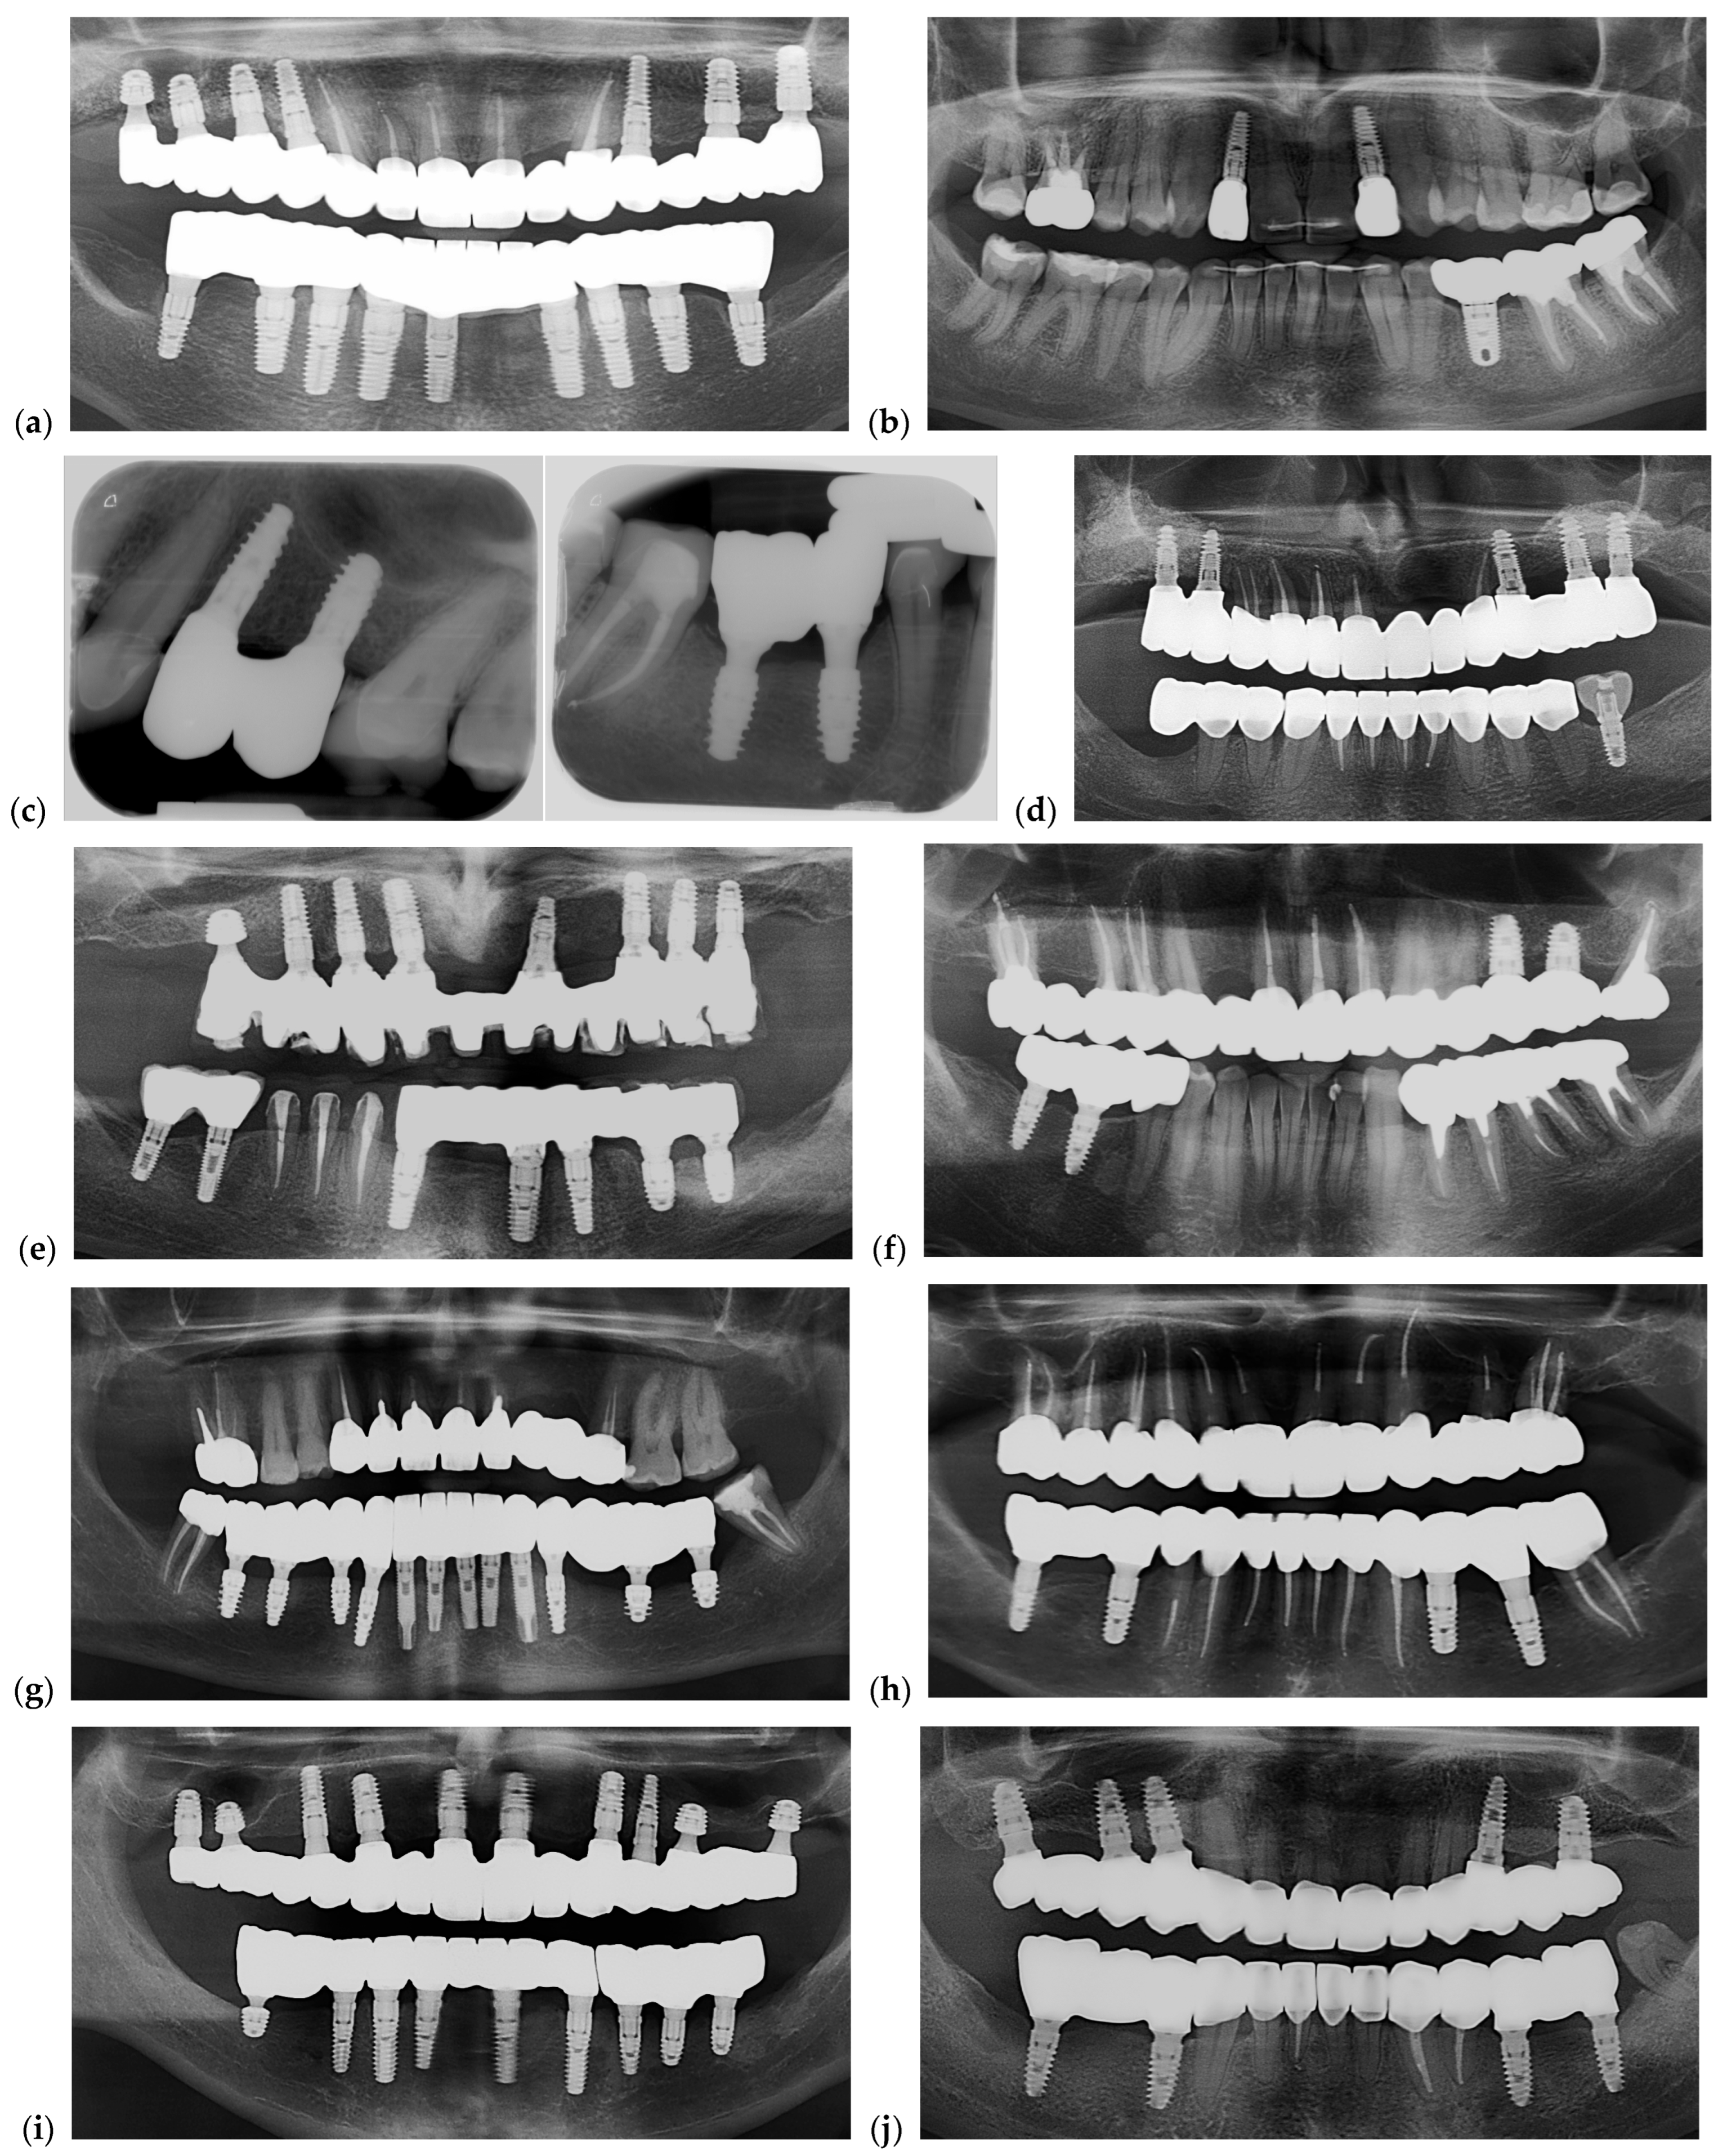

Photos of 5 restorations from selected cases for each group are presented in Figure 16. Radiographic images are shown in Figure 17. Each image from Figure 16 is corresponding with the same position of the Figure 17.

Pictures of dental restorations with (a,c,e,g,i) or without (b,d,f,h,j) the PKT from cases selected for this study.

Figure 17.

Representative radiographs illustrating the seating and adaptation of the analyzed restorations after fixation. (a,c,e,g,i) Restorations with the PKT cap; (b,d,f,h,j) restorations without the PKT cap. Panoramic radiographs were primarily used to document overall fit and implant distribution, while periapical radiographs (panel (c)) were included only in one representative case to confirm marginal seating and screw engagement at higher resolution. All radiographs served as qualitative confirmation of restoration fit following final torque, not for quantitative gap measurement. Each radiograph corresponds to photos in Figure 16.

Both panoramic and periapical radiographs were used to verify restoration seating after fixation. Panoramic views documented overall prosthetic alignment, while periapical images (in one case) confirmed marginal fit and screw engagement at higher resolution